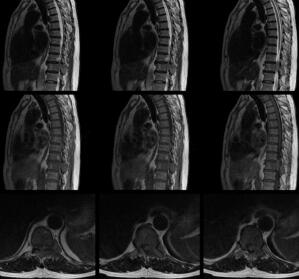

男,64岁,双下肢无力、麻木,10余天(图1)。

图1 胸11椎体左后部、左侧横突及棘突信号减低,左侧椎间孔开大,见低信号肿物向椎管内生长,脊髓受压向右前方移位,椎管内占位上下径线约35.9mm,最大截面约12.5mm×5.8mm。扫描所见肝右叶类圆形长T2小结节,直径约8.2mm